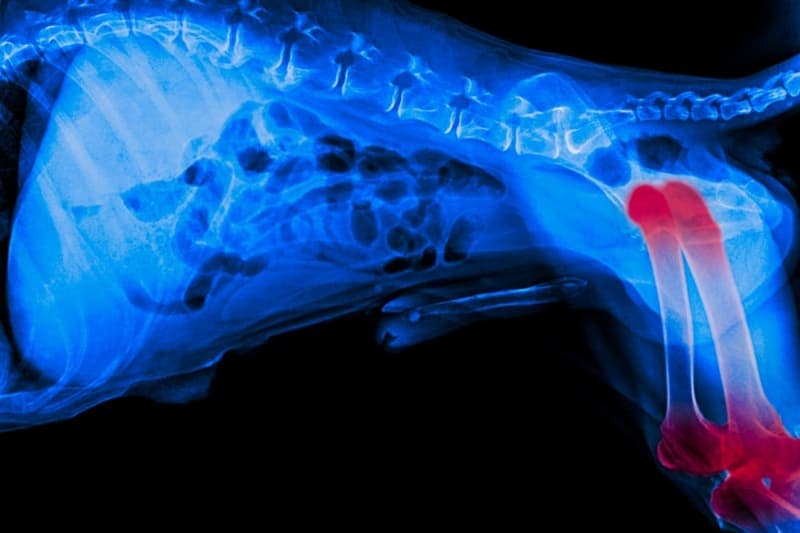

How do vets diagnose arthritis in dogs?

Your vet may suggest diagnostic tests, like x-rays, to confirm and find the changes caused by arthritis. In some cases, blood tests may be needed to rule out any health problems that could be linked to arthritis.